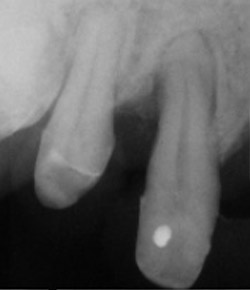

歯周病が進行して、歯の根元まで炎症が広がることがあります。右の写真をご覧ください。赤丸で囲んだ分が黒くなっています。ここは、歯肉が衰え、歯と歯肉の間にできたすき間です。ここに付着した歯石を取り除くことはできません。放置すると歯周病がさらに進行して、やがて抜歯となってしまうでしょう。